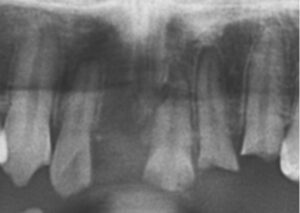

• レントゲンはなぜ撮るの?

レントゲンはなぜ撮るの?

みなさん歯医者に行くと、レントゲンを撮られることがあると思います。 多くの歯科医院でレントゲン撮影は基本的な検査として行われていますが、どうして見れば分かりそうなのにレントゲンをとらないと行けないのかと疑問に思ったことがある方もいると思いま […] 本文を読む